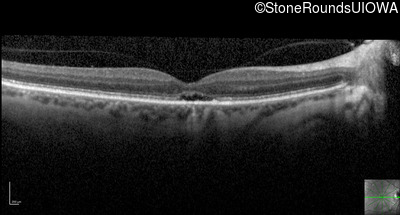

Optical Coherence Tomography - Right - 20/100 -1

Exemplar / OCT Stack

OCT Stack